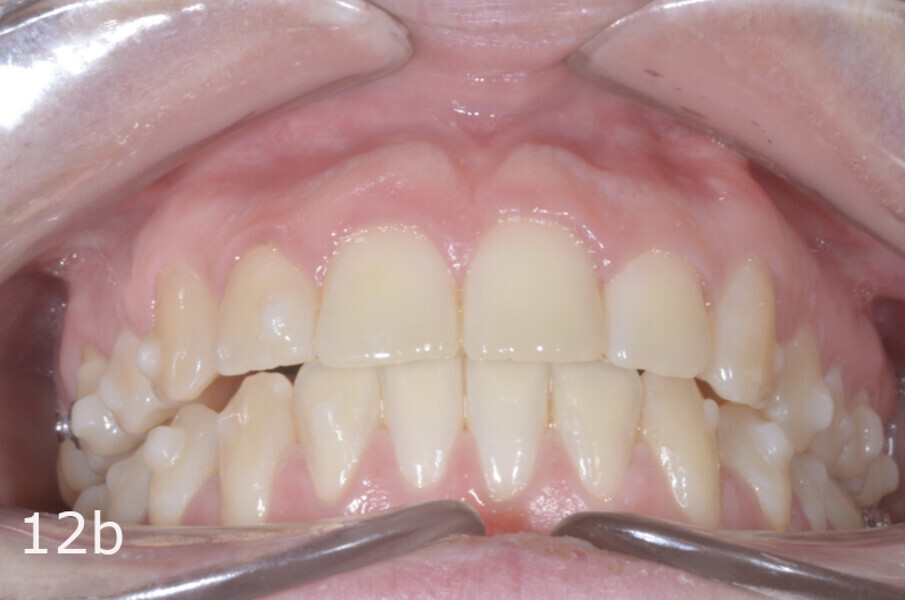

The 23-year-old dolichofacial female patient complained of not being able to chew properly. Facial examination showed a convex profile, an enlarged lower facial height, and a skeletal Class III malocclusion (Figs. 1–3). Intra-oral examination revealed an Angle Class III right subdivision malocclusion, anterior open bite, no overjet and a maxillary dental midline deviated about 3 mm to the right compared with the mandibular dental midline (Fig. 4). The panoramic radiograph confirmed previous extraction of the maxillary right first premolar and the presence of all four third molars (Figs. 5 & 6).

The treatment objectives included closing the anterior open bite, achieving a bilateral Angle Class I relationship and a proper overjet and overbite, correcting the midline discrepancies, and achieving a profile harmonisation. The treatment plan consisted of orthodontic camouflage treatment with asymmetric distalisation in three of the four quadrants using Invisalign aligners (Align Technology) and third molar extraction. The Invisalign Comprehensive package was chosen, and 63 pairs of aligners were used (Figs. 7–10). Each aligner was worn for 20 hours a day for one week each. The use of Class III elastics on both sides was indicated. Afterwards, ten refinement aligners were needed to improve the interdigitation on the right side (Figs. 11 & 12).

The total treatment time was 15 months. An Angle Class I relationship was established along with adequate anterior and canine guidance, establishing a functional occlusion. This not only ensures optimal masticatory function but also protects the teeth and the temporomandibular joint from excessive force. Maxillary and mandibular fixed retention were installed at the end of the treatment (Figs. 13–19).